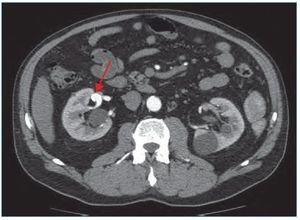

Mediante microcateterismo superselectivo de la rama eferente, se cateteriza el aneurisma y se emboliza mediante coils GDC de liberación controlada (figuras 3 y 4).

Figura 3. Microcateterismo superselectivo de la rama eferente del aneurisma.